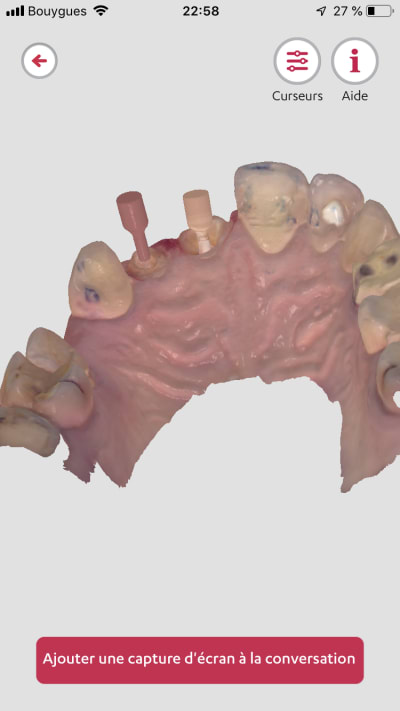

Exemple de ce sue sort une trios 2 de 2013..

Certains d’entre vous ont ils essayé ce type d’ic usiné fibré ?

J’ai reçu un disque pour faire des tests d’usinage ... c’est concluant de ce point de vue.

Reste à savoir s’il peu susciter l’interet au fauteuil .. ( ic issue de ios biensure ) donc ajustage en bouche sans problèmes.

Un exemple de scan avec matching emp pour richmond tenon anatomique sous stellite.

Trios 2 couleur de 2013...